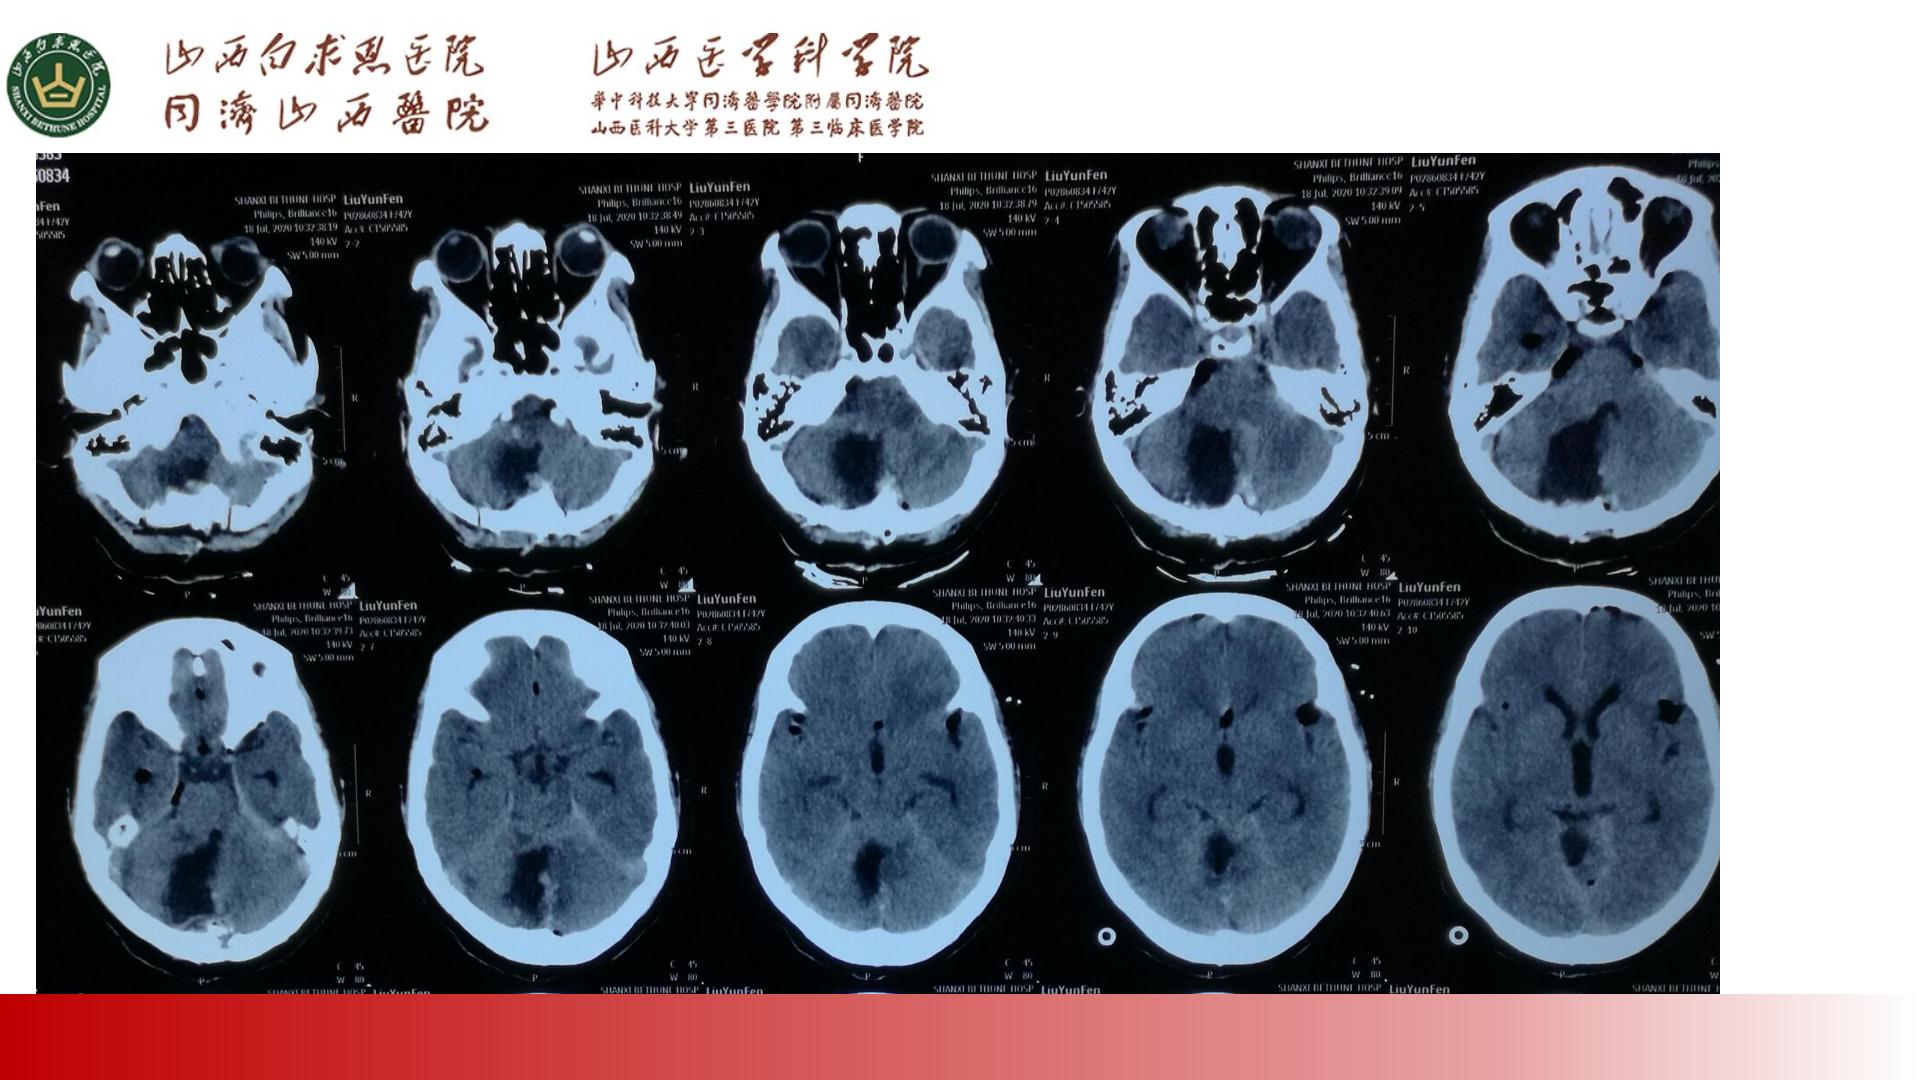

PPT:两例小脑节细胞胶质瘤治疗体会